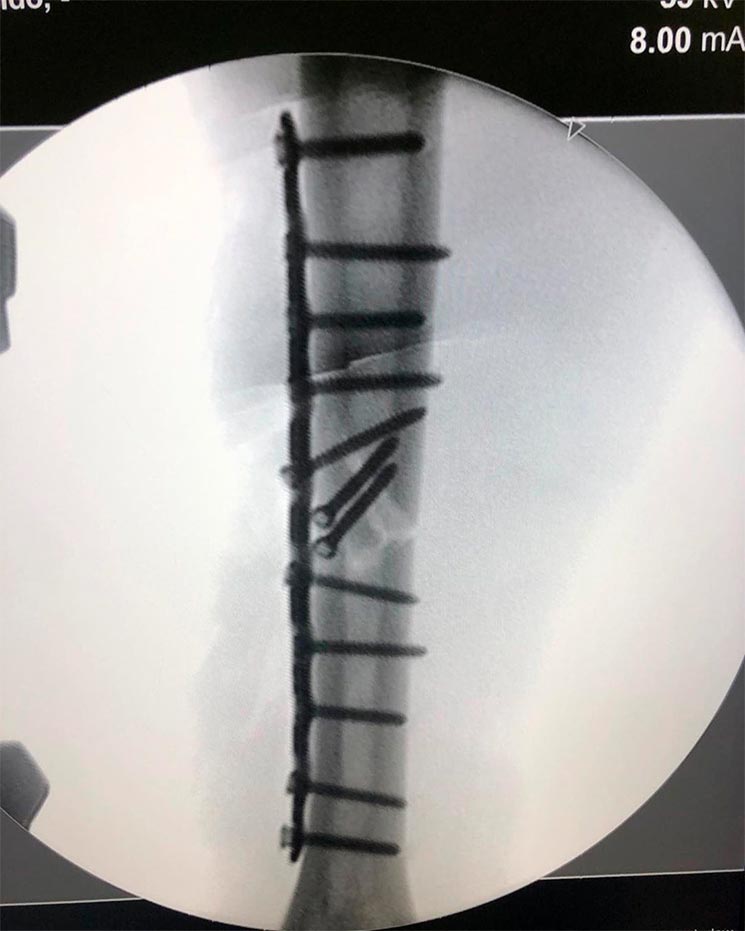

En la primera imagen, tomada en 3D, se puede apreciar perfectamente la fractura en el húmero derecho de Marc, en la zona media del hueso, por fortuna sin afectación al nervio radial. En la segunda imagen, ya se puede ver la fractura totalmente fijada con una placa de titanio de última generación anclada con hasta 12 tornillos, una placa que el propio Dr. Mir denominó 'bloqueada' y que está fijada al húmero por 10 tornillos, escondiendo dos de ellos en el interior del hueso en la zona exacta donde se partió.

Aquí puedes ver las dos imágenes que Marc ha compartido a través de sus redes sociales: